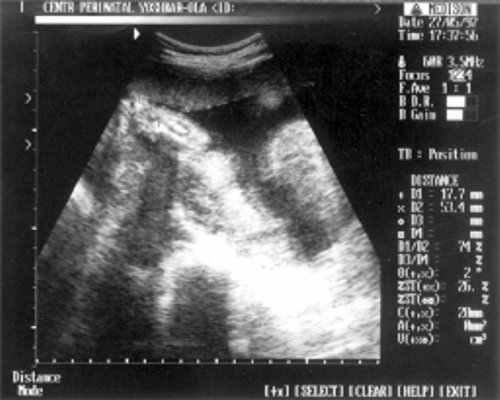

- Плечевая кость = 16 мм - 14,5 нед. (рис. 3)